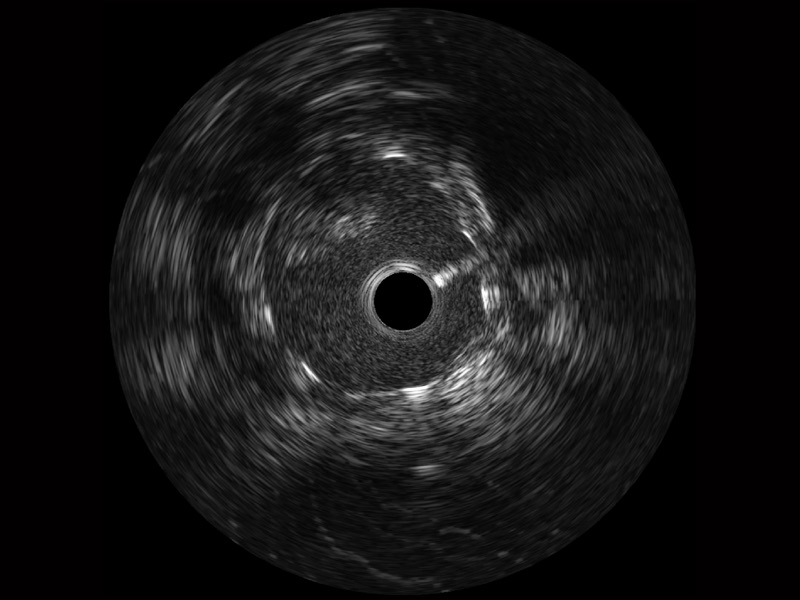

一键智能描迹,自动测量斑块负荷、面积狭窄率等指标,准确率高于90%